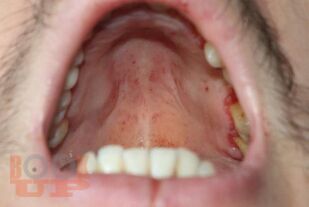

В учебном пособии представлены дифференциально-диагностические признаки проявлений коронавирусной инфекции от основных заболеваний слизистой оболочки рта, позволяющие врачу-стоматологу систематизировать полученные знания.

Пособие предназначено для врачей-стоматологов разных специальностей: терапевтов, ортодонтов, общей практики, хирургов, ортопедов. Пособие может быть использовано для подготовки к аккредитации врачей по специальности «Стоматология терапевтическая», а также врачами ординаторами как дополнительная учебная литература.